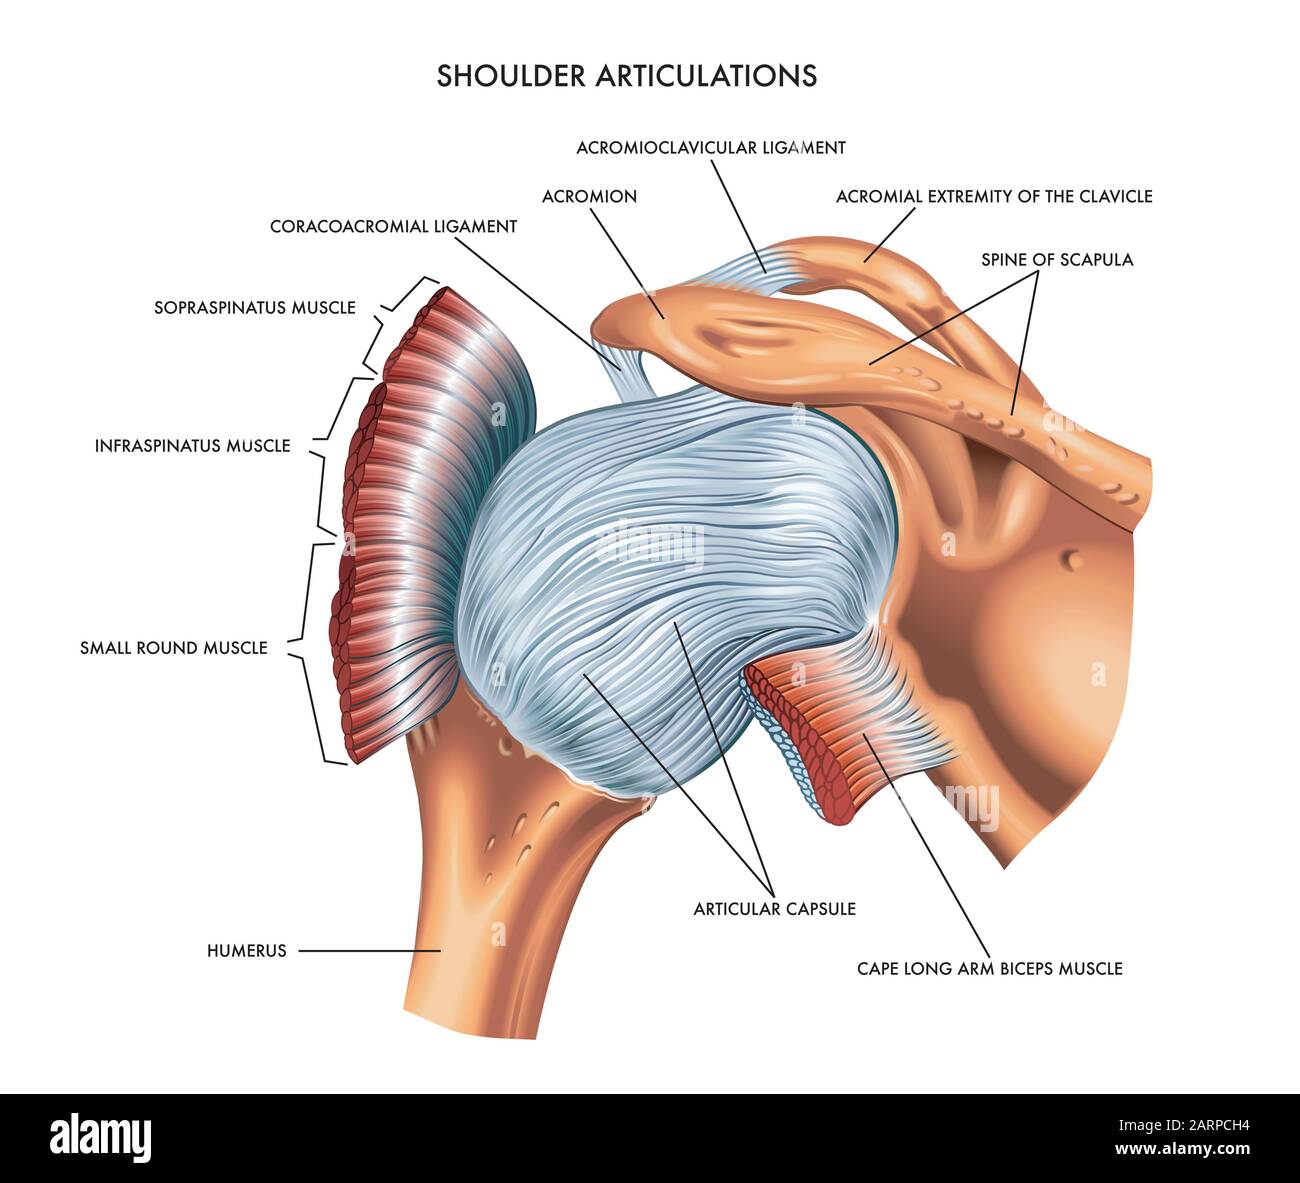

A detailed medical illustration of shoulder articulations. Stock Photohttps://www.alamy.com/image-license-details/?v=1https://www.alamy.com/a-detailed-medical-illustration-of-shoulder-articulations-image341626912.html

A detailed medical illustration of shoulder articulations. Stock Photohttps://www.alamy.com/image-license-details/?v=1https://www.alamy.com/a-detailed-medical-illustration-of-shoulder-articulations-image341626912.htmlRF2ARPCH4–A detailed medical illustration of shoulder articulations.